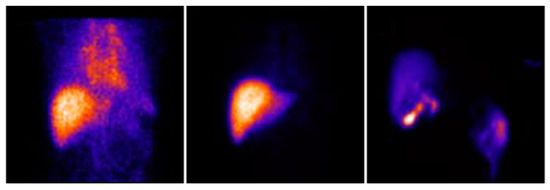

- Gupta, M.; Choudhury, P.S.; Singh, S.; Hazarika, D. Liver functional volumetry by Tc-99m mebrofenin hepatobiliary scintigraphy before major liver resection: A game changer. Indian J. Nucl. Med. 2018, 33, 277–283. [Google Scholar] [CrossRef]

- de Graaf, W.; Bennink, R.J.; Vetelainen, R.; van Gulik, T.M. Nuclear imaging techniques for the assessment of hepatic function in liver surgery and transplantation. J. Nucl. Med. 2010, 51, 742–752. [Google Scholar] [CrossRef]

- Iimuro, Y. ICG clearance test and 99mTc-GSA SPECT/CT fusion images. Visc. Med. 2017, 33, 449–454. [Google Scholar] [CrossRef]

- Kotani, K.; Kawabe, J.; Higashiyama, S.; Yoshida, A.; Kawamura, E.; Tamori, A.; Shiomi, S.; Kawada, N. Heterogenous liver uptake of Tc-99m-GSA as quantified through SPECT/CT helps to evaluate the degree of liver fibrosis. Medicine 2018, 97, e11765. [Google Scholar] [CrossRef]